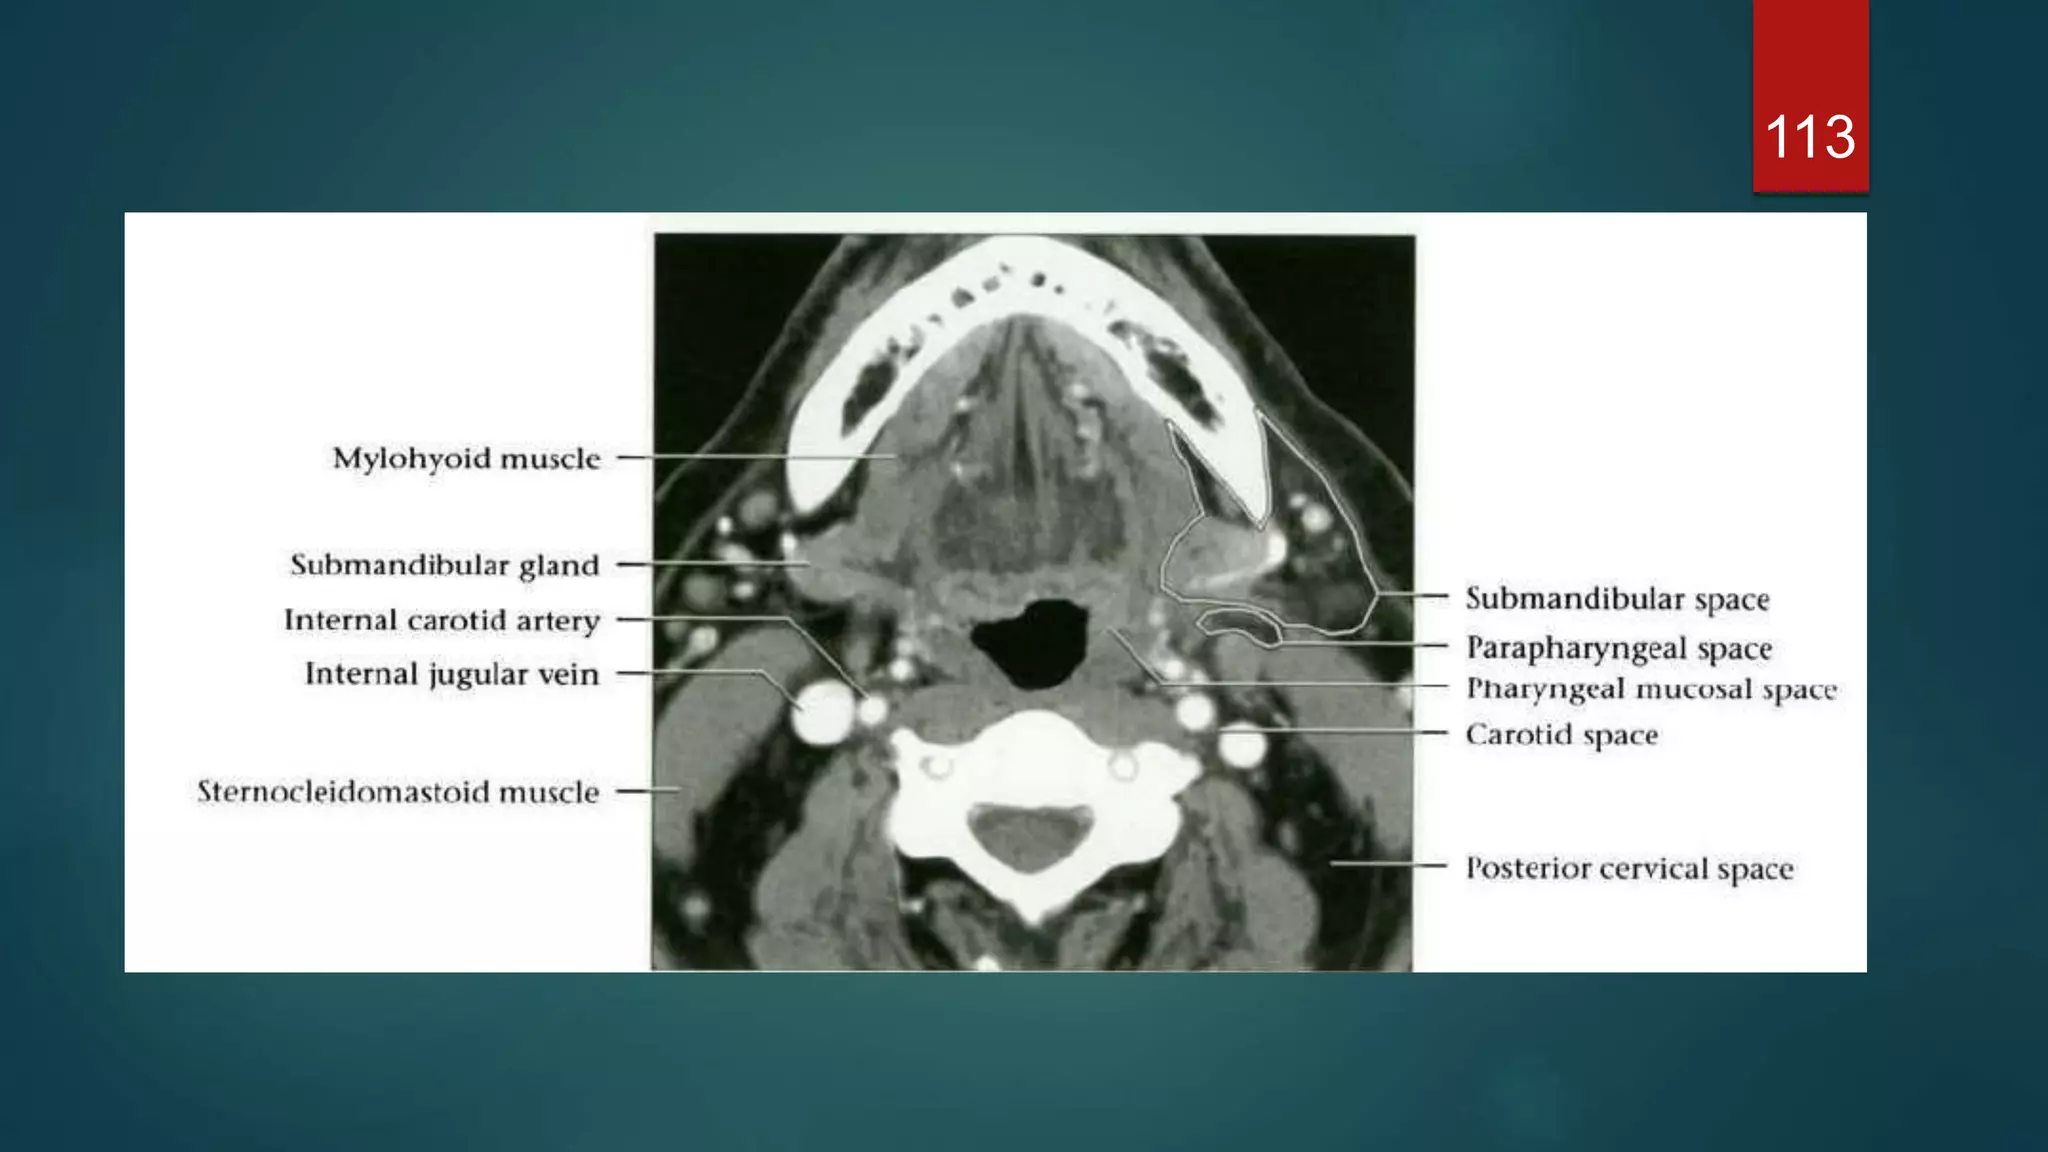

SUBMANDIBULAR SPACE

 Extend : Mylohoid superiorly & hyoid

bone inferiorly.

 Communicates freely with sublingual

space.

 Contents : superficial portions of the

Submandibular gland, submental and

submandibular LNs, facial artery and

vein, fat and ant belly of digastric.

CAROTID SPACE

 Paired tubular structure traversing SHN

and IHN

 Skull base to superior mediastinum

 Lateral to RPS

 Enveloped by carotid sheath : all 3

layers of DCf

 Contents : SHN – ICA IJV , CN9-12,

:IHN - CCA, IJV , CN10 trunk (

vagus)

113